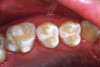

9. Apply the sealant over the pits and fissures (Figure 10). Avoid over manipulation to prevent producing air bubbles. Cover all the pits and fissures, but do not overfill to a high, flat surface.

Fig 5. Clean the tooth surface with a slurry of pumice and water, a bristle brush with clear water, or an air-powder polisher.

Figure 5

Fig 9. Dry the tooth surface again with compressed air for a minimum of 10 seconds. A properly etched surface appears white, dull, and frosty.

Figure 9